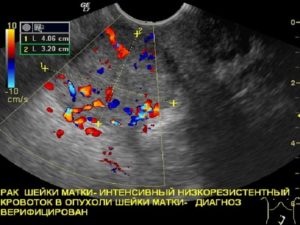

Дополнительными методами исследования выступают УЗИ, рентгенография, сцинтиграфия, МРТ и КТ и прочие.

Лучевая терапия может проходить дистанционно или быть внутриполостной (брахитерапия). Дистанционная лучевая терапия проводиться на линейных ускорителях (на фото).

При помощи брахитерапии возможно проведения больших доз облучения прицельно, в опухолевый очаг, не затрагивая здоровые ткани.

Лучевая терапия в комплексе с химиотерапией становится единственно возможным методом лечения, так как рак носит местно-распространённый характер и не может быть удалён при помощи операции.Современные технологии позволяют использовать несколько видов лучевой терапии: внутриполостная и дистанционная.

Внутриполостная технология подразумевает контактное воздействие с опухолью, такими источниками как кобальт, цезий или иридий.

Дистанционное облучение необходимо в первую очередь для облучения регионарных лимфатических узлов и других возможных метастаз в области таза.